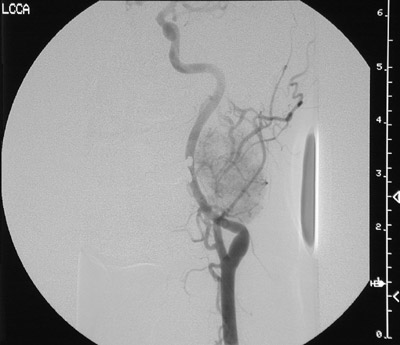

This angiogram reveals a blush of contrast outlining a paraganglioma that is adjacent to the bifurcation of the common carotid artery on the left. These tumors, like endocrine lesions in general, are highly vascular.